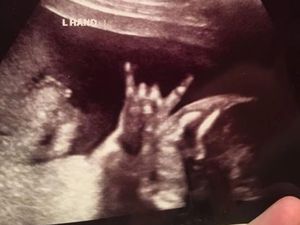

Ada 'Yesus' di Hasil USG Bayi di Pennsylvania

Pasangan orang tua di Pennsylvania dikejutkan dengan hasil USG bayi mereka. Pasalnya, mereka melihat penampakan 'Yesus' di hasil USG tersebut.